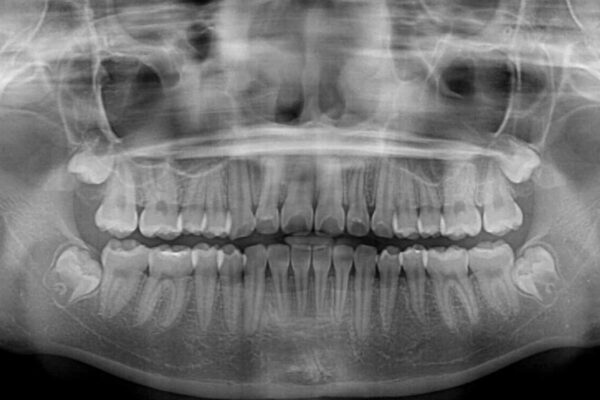

治療前

• インビザラインは使える自信がない ワイヤー装置にて矯正治療 治療前画像